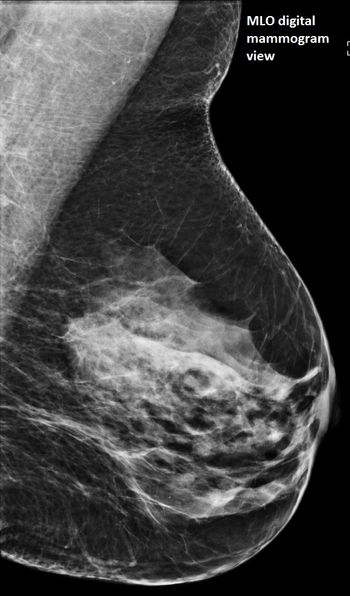

49-year-old patient presented for bilateral screening mammogram as well as bilateral screening ultrasound due to dense breast tissue.